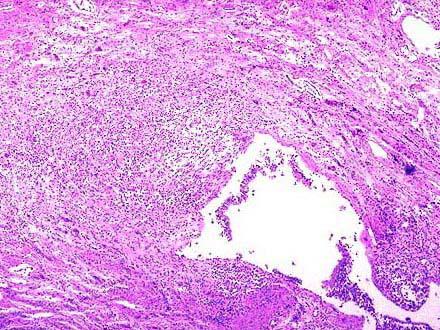

问题 患者,女,25岁,长期慢性咳嗽伴大量脓臭痰,反复咯血。手术切除病变肺叶,巨检如图,镜检如图所示,确切的诊断是 ( )

选项 A.慢性支气管炎 B.支气管扩张症 C.肺结核 D.肺脓肿 E.弥漫性泛支气管炎

答案 B